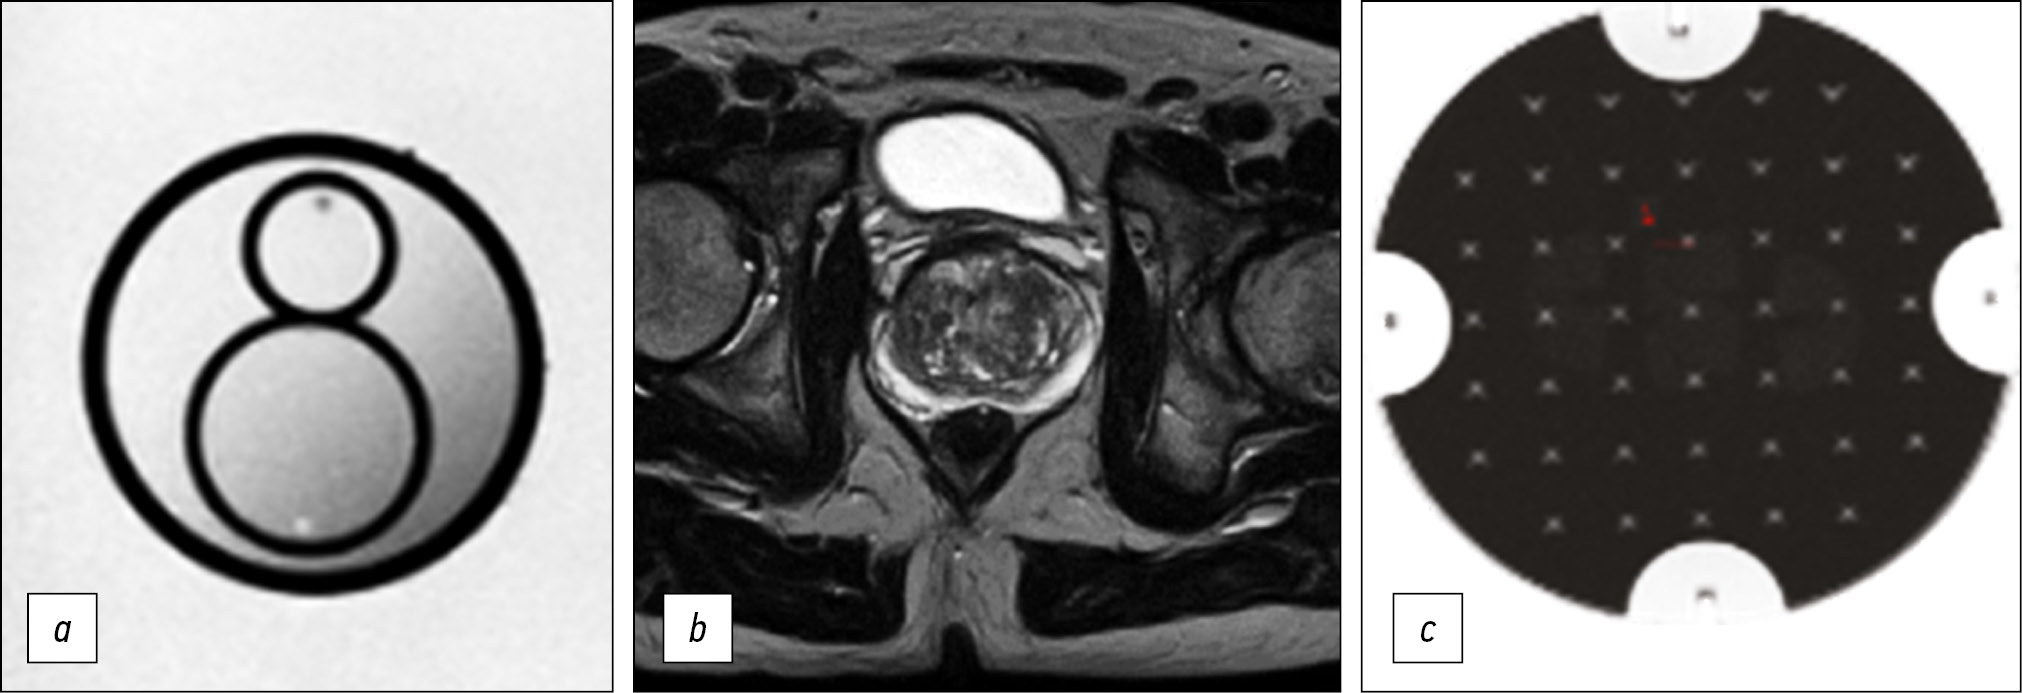

Fig. 3. Medical organization 2 (MO 2). In the peripheral zone on the right, a hypointense zone on T2-WI and ICD map adjacent to the capsule (arrows) is defined: a) T2-WI, axial projection (TR 6006, TE 75, FOV 30×25 cm, Matrix 256×256); b, c) DWI and ICD (TR 9377, TE 80, FOV 37×30 cm, Matrix 128×192).

Note. Here and in Figures 3–5: T2-WI, T2 weighted images; DWI, diffusion-weighted images; MDC, measured diffusion coefficient; TR, repetition time; TE, echo time; FOV, field of view; Matrix is a matrix.

Thus, in all presented HO MHD, the requirements recommended by PI-RADS v2.1 for the presence of T2-WI in the axial and at least one additional (sagittal and/or coronal) views were met. In addition, it should be noted that the recommended layer thickness for T2-WI in the axial view should be no more than 3 mm, while in HO 2 and HO 3, it is 4 mm (Figures 3 and 4). The same is true for HO 1, where the DWI slice thickness is 5 mm with the recommended 4 mm or less (Figure 2). An important factor is the field of view; according to PI-RADS v2.1, field of view (FOV) values for T2-WI should be 12–20 cm, while in HO 1 and HO 3, the field of view is much larger (30 × 35 cm and 40 × 30 cm, respectively) (Figures 2 and 4). According to PI-RADS v2.1, the recommended field of view for DWI is 16–22 cm, although none of the three HOs adhere to this standard. The fact of the variability of the FOV values and the section slice thickness inevitably affects the resolution and, as a result, the ability to detect lesions.